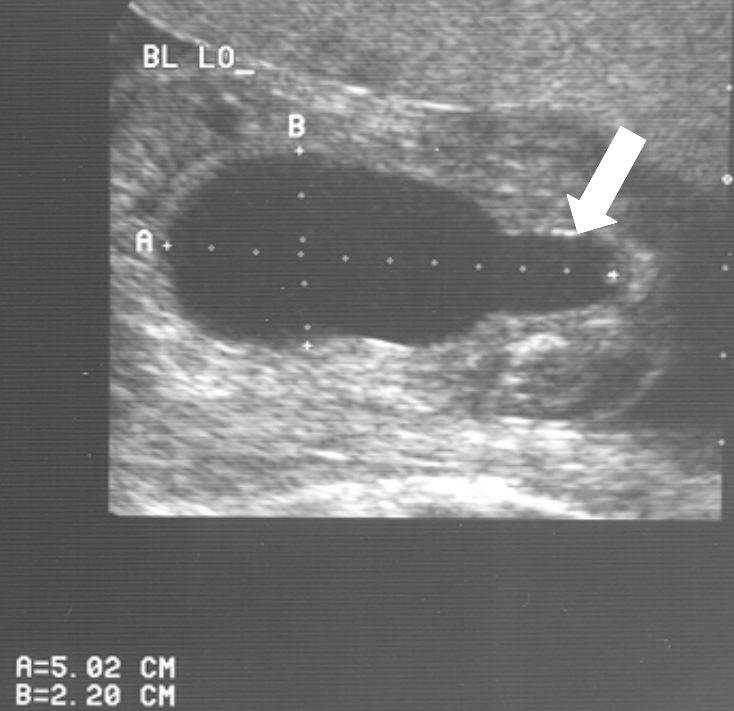

Diagnose vóór de geboorte

Veel ernstige vormen van urethrakleppen worden al gezien bij echografisch onderzoek vóór de geboorte. Bij de 20 weken echo (of misschien in de toekomst bij een 13 weken echo) worden verwijde nierbekkens en urineleiders gezien. De blaas kan dikwandig zijn, maar ook zeer groot en uitgerekt. Vaak kan het verwijde deel van de plasbuis ónder de blaas worden gezien. Dat noemen we het “sleutelgat teken” omdat de blaas in lengtedoorsnede op de echo er dan uitziet als een sleutelgat. De hoeveelheid vruchtwater kan normaal of verminderd zijn. Als er een verdenking is op urethrakleppen wordt de bevalling gedaan in een centrum waar direct optimale zorg kan worden geleverd aan de pasgeborene.

Een ernstige vorm van urethrakleppen wordt niet altijd gezien bij de 20 weken echo. De meeste van deze jongens presenteren zich dan kort na de geboorte met een urineweginfectie.

20 weken echografie: links: dikwandige blaas met verwijding van de plasbuis tot aan de kleppen (pijl): het “sleutelgat teken”. Onder: verwijde urineleiders. Bij kinderen gaan de urineleiders bij verwijding ook erg gekronkeld verlopen.

Verwijde nierbekkens (lange pijl) en nierkelkjes (korte pijl). Smalle nierschors.